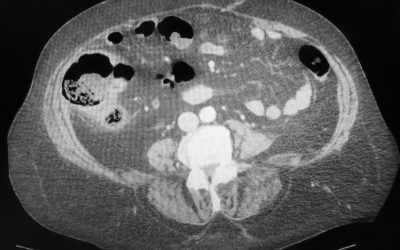

Nodulo intra-pancreatico non metastatico evidenziabile con RMN e 68Ga-DOTA-peptide PET/TC: resezione pancreatica o agobiopsia eco-endoguidata?

di Enrico Ganz l riscontro accidentale di un isolato nodulo intrapancreatico non metastatico nel corso di una tomografia computerizzata (TC) pone il problema di comprendere se sia opportuno un trattamento chirurgico, un periodico controllo della lesione o...